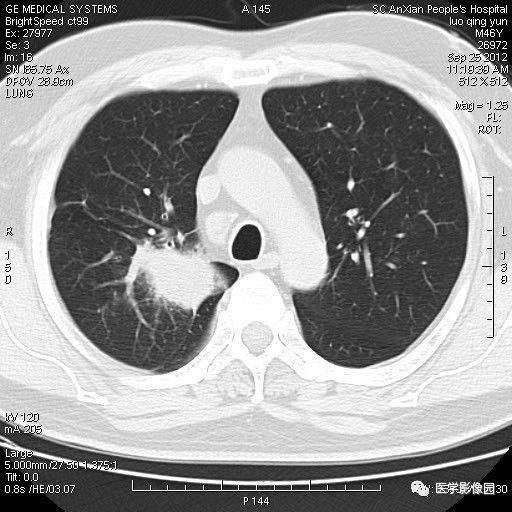

影像学诊断为:考虑右上肺癌伴肺内转移,请结合临床。

临床医生根据影像学诊断情况建议刘大爷转上一级医院进一步检查确认。刘大爷及家属得知该诊断结果后,心急如焚,在其后20多天的时间里,辗转多家医院进行治疗,后到上海某医院住院,出院诊断为肺炎性假瘤。